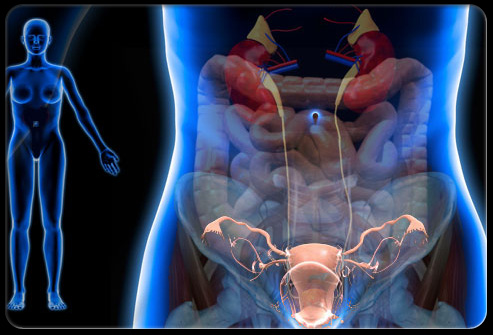

卵巢囊肿

盆腔疼痛怎么引起的,盆腔疼痛是什么原因引起的

卵巢囊肿是由卵泡排卵失败或卵泡排卵后重新闭合后产生的液体在卵巢中形成的组织。卵巢囊肿有很多种类。常见症状包括:尖锐的盆腔疼痛、月经不调、盆腔压力大、和*交性**痛。卵巢囊肿尺寸大时尤其容易出现盆腔疼痛和排尿痛,虽然大多数囊肿会自行消失,不过有些囊肿需要通过药物或手术去除。

子宫肌瘤

子宫肌瘤是生长在子宫壁上的良性肿瘤。有些子宫肌瘤会导致盆腔疼痛、*交性**痛、盆腔压痛,并可能影响一些女性的受孕能力。子宫肌瘤在三四十岁的女性中最常见。有这些症状的女性应该去妇科门诊就诊。治疗手段包括对症用药或手术剃除。